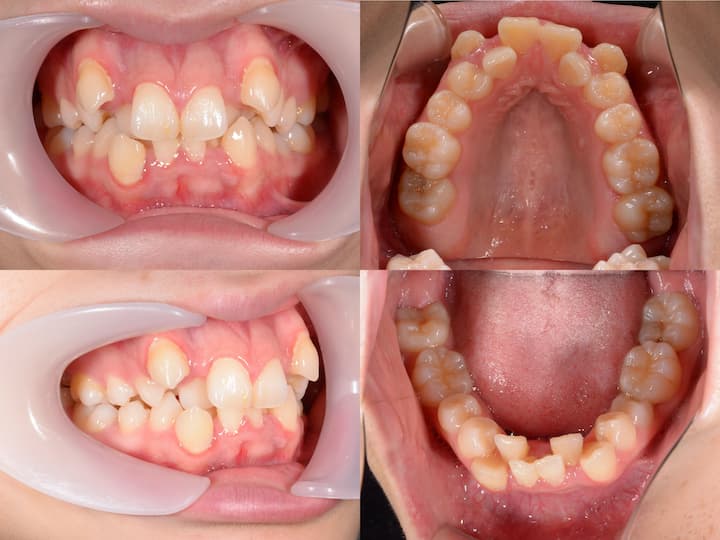

反対咬合のハーフリンガル矯正

Before

After

治療期間: 1年8カ月

前歯の反対咬合と下顎骨の右側偏位を、左下4番抜歯を伴うハーフリンガルで治療しました。

初診時年齢3110ヶ月の患者様です。前歯の反対咬合と下顎骨の右側偏位に対し、左下4番目の歯を抜いてスペースをつくった後、下の前歯を左後方に移動しました。上の歯は裏側に、下の歯には表側に矯正装置をつけるハーフリンガル矯正を行いました。治療後は反対咬合も改善され、噛み合わせたときに上の前歯が下の前歯よりも前にくるようになりました。また、上下の歯の中心も合わせることができました。

反対咬合を改善させる過程では、前歯の干渉により、咬合性外傷(噛み合わせの力が強いことによって歯や歯周組織、顎関節などを損傷すること)を生じるリスクがあります。そのため、こちらの症例では奥歯の高さを調整することで前歯の当たりを調整しながら治療を進めました。